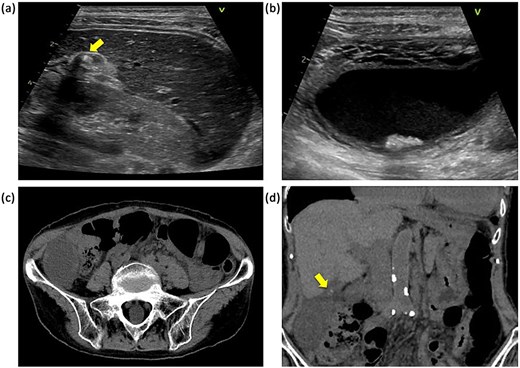

The laboratory data on admission were: white blood cell count, 7.7 × 103/μl; C-reactive protein concentration, 3.07 mg/dl. Abdominal ultrasound revealed a gallbladder stone in the cystic duct and gallbladder enlargement. The gallstone was located in the neck of the gallbladder (Fig. 1a). The gallbladder wall was thickened in a mesh-like pattern up to 11 mm on the ventral side, and there was lamellar wall thickening of 3 mm on the dorsal side (Fig. 1b). Computed tomography (CT) demonstrated an enlarged gallbladder and a gallstone lodged in the gallbladder neck (Fig. 1c and d). Contrast-enhanced CT was not performed because of the patient’s poor renal function. We initially diagnosed the patient with gallstone cholecystitis, because the abdominal symptoms were not severe and an abdominal ultrasound revealed a gallstone in the cystic duct with thickening of the wall leading to the gallbladder. In addition, given the patient’s history of chronic heart failure and chronic atrial fibrillation, and the fact that she was taking apixaban (Bristol-Myers Squibb Company and Pfizer Inc., Tokyo, Japan), we considered the surgical risk to be high (Charlson comorbidity index score of 6 points) and initiated antibiotic treatment. On the second day after admission, there was no worsening of the inflammatory findings or abdominal symptoms, but the symptoms persisted, so the decision was made to wait until the effects of apixaban had worn off before performing surgery. Preoperative magnetic resonance imaging could not be performed due to scheduling constraints. Laparoscopic cholecystectomy was performed on the third day of hospitalization. Intraoperatively, gallbladder torsion and necrosis were noted: the gallbladder had rotated 180° in a clockwise direction and the cystic duct was obstructed (Fig. 2a). The surgery took 50 min and was completed with minimal bleeding. Due to the high risk to the circulatory system, the patient was managed in a high-care unit after surgery. There were no complications, so she was discharged on postoperative Day 8. Histopathological examination of the gallbladder revealed acute on chronic cholecystitis with transmural neutrophil infiltration, edema, hemorrhage, and necrosis (Fig. 2b).

Abdominal ultrasonography and CT findings. (a) Impacted gallstone in the gallbladder neck (arrow). (b) Enlarged gallbladder and edematous thickening of the gallbladder wall. (c) Enlarged gallbladder in the right lower abdominal quadrant. (d) Enlarged gallbladder and gallstone in the neck of the gallbladder (arrow).